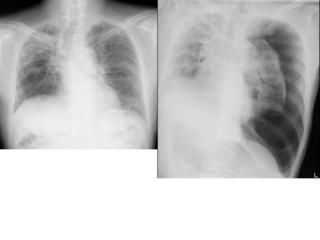

Aシルエット・サインを使う

陰影があったときに、果たしてその陰影はどこにあるのか。

上、中、下肺野のどこにあるかとともに、シルエット・サインをうまく使うことでどのセグメント(

1〜10に分かれている、例のやつ)を絞り込むことができます。